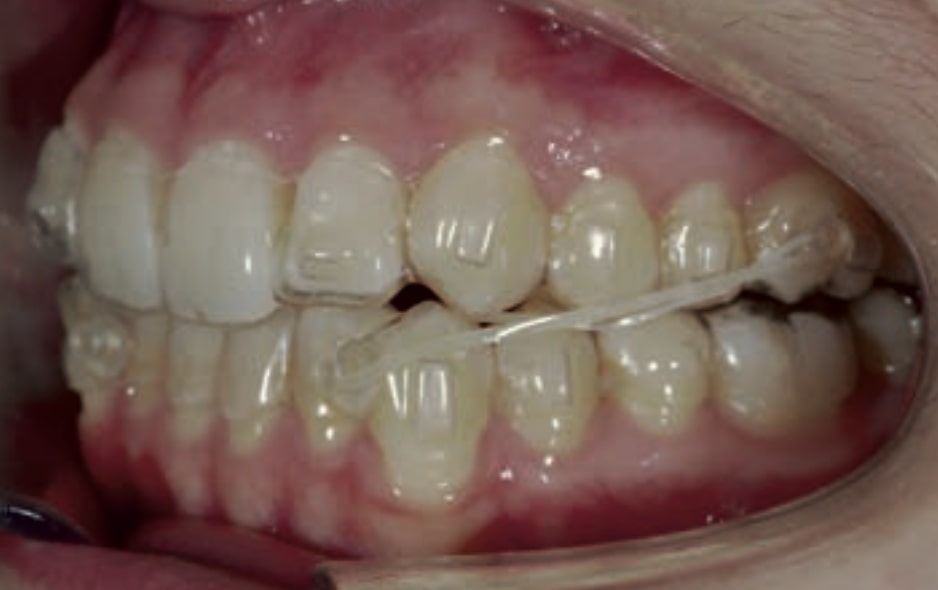

• Distalization of the Third and Fourth Quadrants: Move the teeth distally in these quadrants to achieve a Class I relationship using the A8 protocol, improving the patient’s dental alignment and occlusion.

Treatment setup

Treatment progress